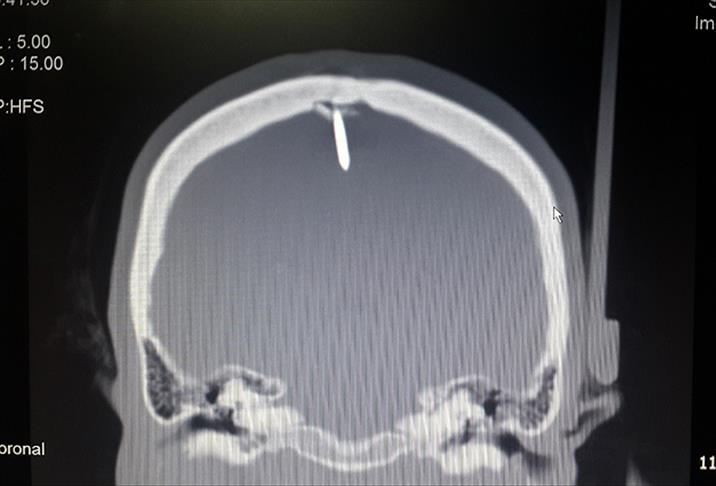

AA muhabirinin edindiği bilgiye göre, bir fabrikada işçi olarak çalışan 45 yaşındaki Şahin, 14 Şubat'ta ayağının kayması sonucu çivi tabancasının üzerine düştü. Kafasına montaj çivisi saplanan kadın, işyerindeki arkadaşlarının yardımı ile Adnan Menderes Üniversitesi (ADÜ) Acil Servisi'ne kaldırıldı. Çekilen beyin tomografisinde, kafatasını delen 2,5 santimetre uzunluğundaki çivinin bir kısmının beyne de zarar verdiği belirlendi.

"Çivinin girdiği bölgeyi hastayı uyuttuktan sonra yarmaya başladık. Çok risk taşıyan bir operasyon olduğu için en ufak bir hataya meydan vermeden kafasından bir parça kemik çıkartıp pencere açtık. Damarları koruyan bölgeye zarar verilmesi halinde hastanın yüksek hayati risk taşıması söz konusuydu. Çivinin beynin motor fonksiyonları yöneten kısmına sadece birkaç milimetre uzaklıkta olması bizi korkutsa da son derece başarılı bir operasyonla 2,5 santim uzunluğundaki çiviyi çıkarttık. Daha sonra aynı bölgeyi yine operasyonla kapattık."